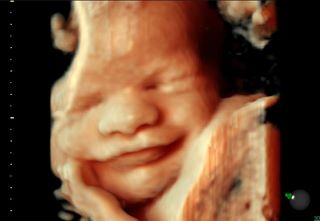

Te presentamos con orgullo nuestro nuevo Ultrasonido HD live* 4Dcon un realismo anatómico excepcional, que ayudara a un mejor diagnostico y al aumentar la percepción de profundidad nos da una imagen fiel en Alta resolución (HD) de cómo luce el bebe. Es una experiencia única que no te puedes perder!

El estudio te revela con detalle inigualable la carita o facciones de tu bebé y su conformación general, gracias a sus herramientas de medición mas exactas descarta malformaciones fetales externas, o las detecta a tiempo oportuno. Si quieres conocer la cara de tu bebé te recomendamos este estudio entre la semana 24 y 32, ya que el tamaño de tu bebe es lo suficientemente grande para admirar sus facciones, También se puede realizar durante todo el embarazo antes de la semana 34, ya que mientras mas grande el bebé mas difícil sera apreciar con facilidad su rostro, ya que a partir de esta semana de embarazo comienza a posicionare para salir.